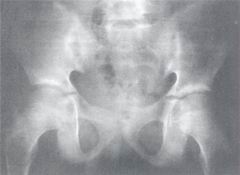

3、關節腫痛,這是最主要的症狀,常發生在發熱後數周或數月,最初常先侵犯膝、踝關節,以後可發展到腕、肘、肩、頸椎等關節。多為兩側對稱性,部分患兒呈遊走性。此外,有的患兒還可伴發貧血、心包炎、心肌炎、胸膜炎、肺炎等。

2、多關節型:發熱等全身症狀較少較輕,而以關節腫痛為主。一般超過5個關節,呈對稱性,多見於膝、踝、腕、手、足關節,常反覆發作,數年後可出現關節畸形。

3、少關節型:一般無全身症狀和關節外表現,僅累及1—5個關節,多為膝、踝等大關節的腫痛。不過,這三型之間可以轉換,全身型和少關節型可以轉為多關節型,多關節型最後可能形成少數關節變形。